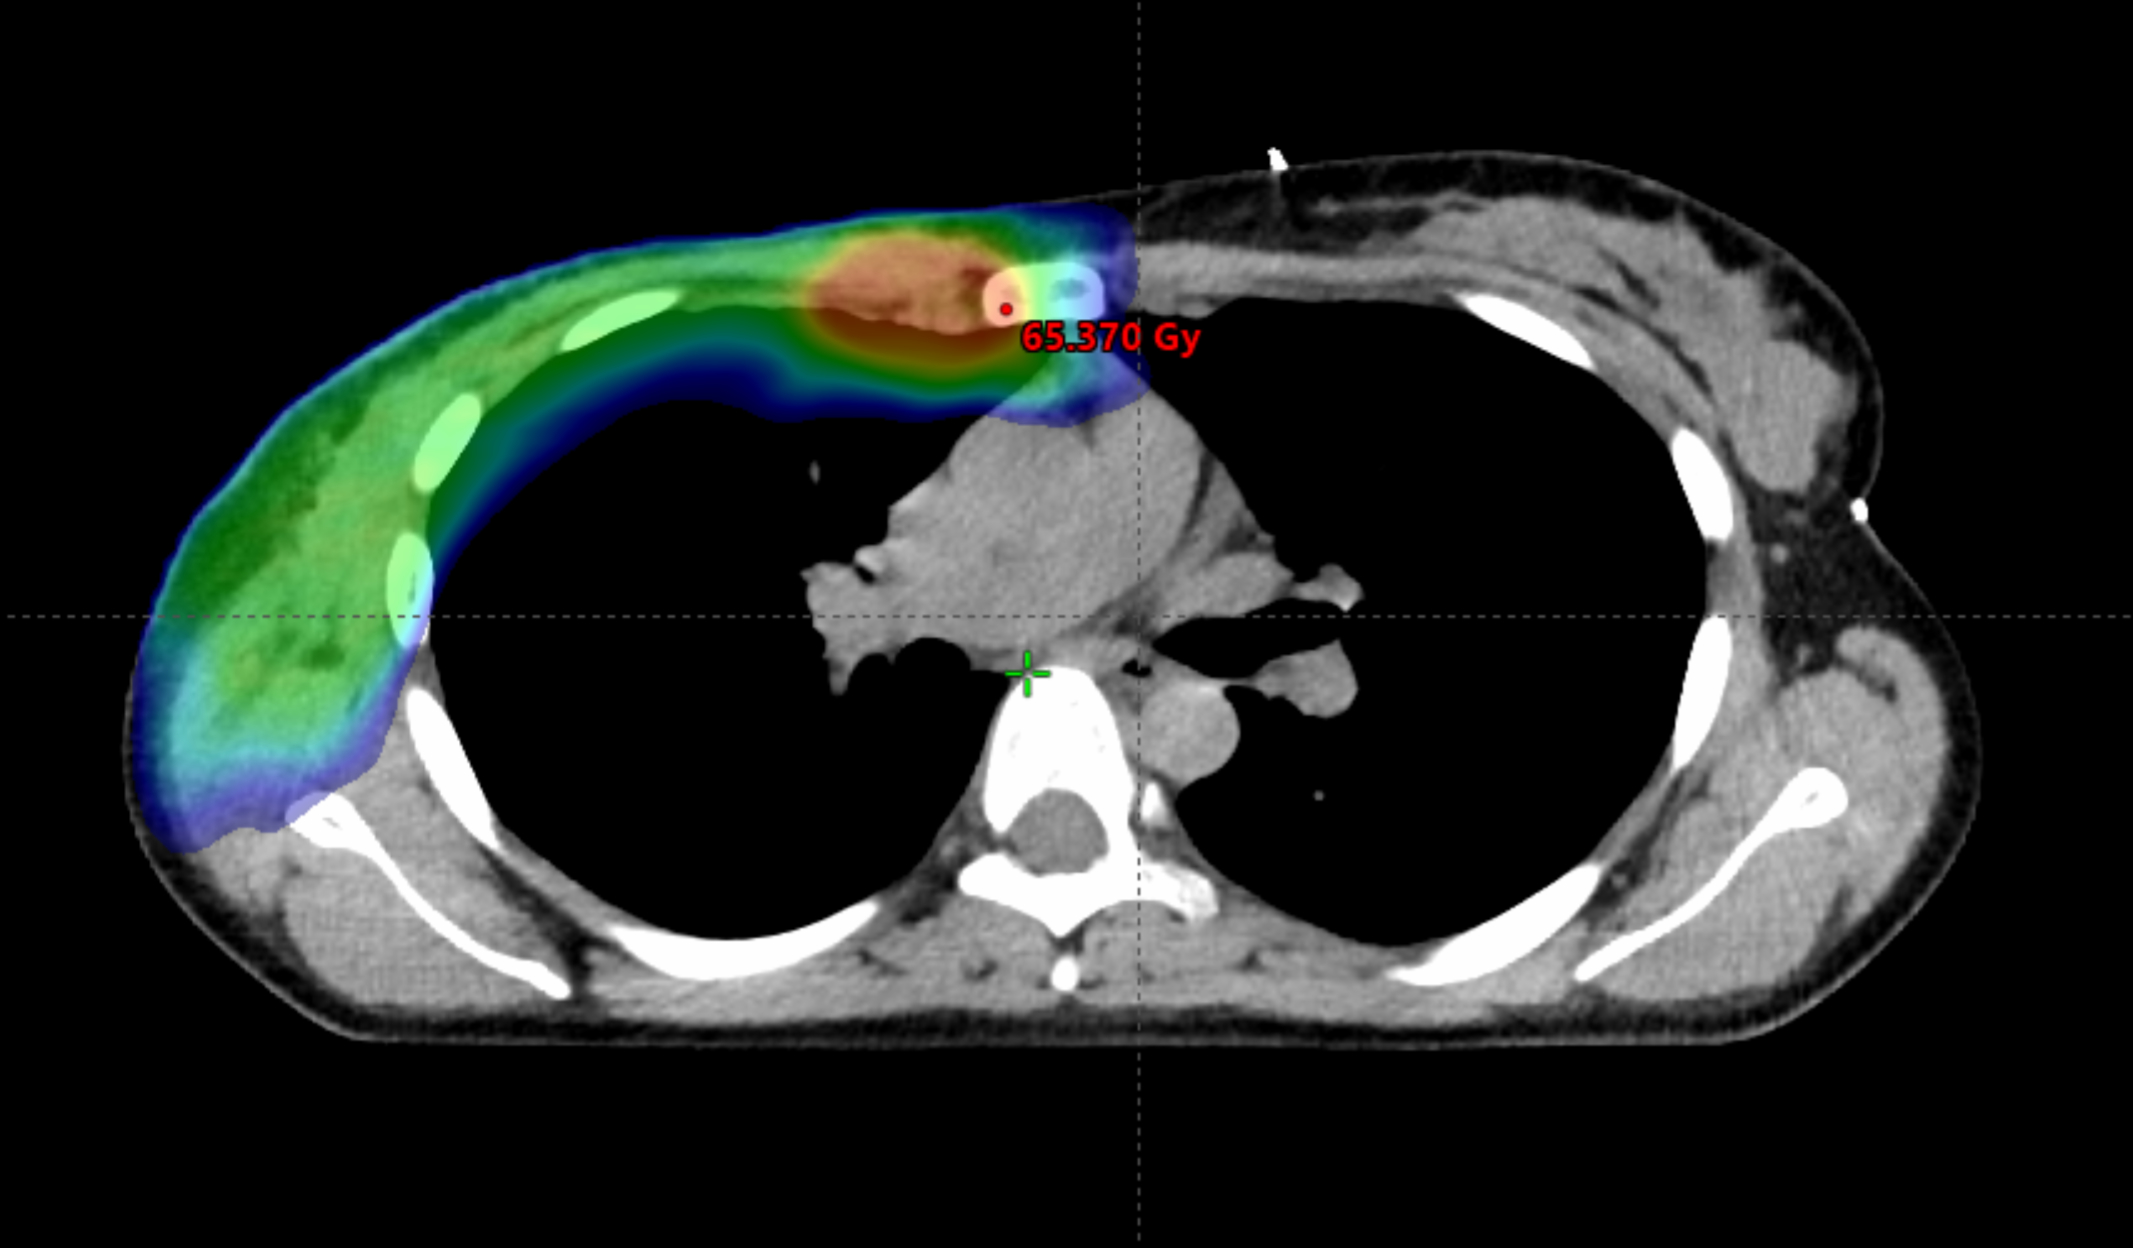

Figure 5

Modern radiotherapy techniques make it safe to boost the dose to the internal mammary lymph nodes. However, prior to implementing this approach, it is crucial to ascertain whether the internal mammary lymph nodes were involved and to determine the specific intercostal region affected. The irradiated volume is graphically represented, the area receiving a lower dose is in blue, while the boost area is in red.